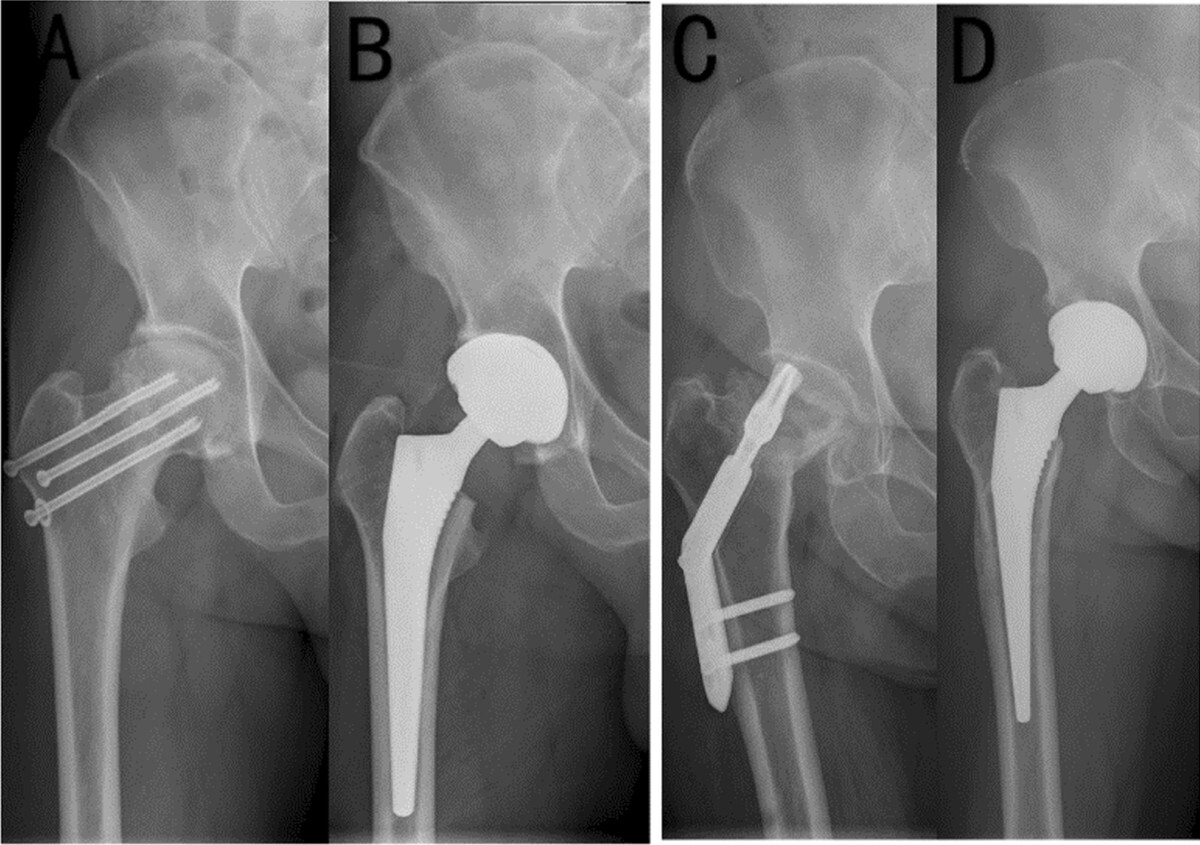

Worldwide, HA remains the most frequently performed procedure for displaced FNFs, particularly in patients over 70 years of age or those with significant medical comorbidities.11,19 (Figure 1) Although technically less demanding and faster to perform than THA, HA offers a lower risk of dislocation and reliably restores mobility in frail, low-demand patients. However, these short-term advantages are counterbalanced by long-term risks, including acetabular erosion, inferior functional outcomes compared with THA, and, in some cases, the subsequent need for conversion to THA.53

THA has increasingly been adopted for the management of displaced FNFs in selected patients, particularly those who are younger, higher functioning, and medically fit. Evidence consistently shows that THA offers superior functional outcomes compared to HA, although at the cost of higher complication rates. (Figure 2)

Registry data corroborate these findings with the Swedish registry PROMs consistently reporting higher satisfaction and functional scores after THA compared with HA.20 Conversion of HA to THA for acetabular erosion restores function but carries higher revision and complication rates than primary THA.75 (Figure 3)